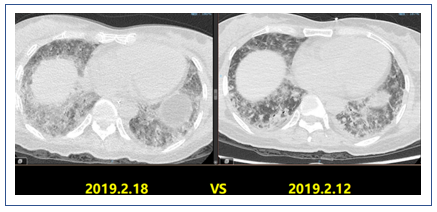

2019年2月25日患者胸部CT示双肺病变较前吸收(图16)。

2019年1月25日,患者胸部CT显示双下肺实变较前有所吸收(图11)。

2019年2月1日患者胸部CT显示,上肺渗出进展(图14)。